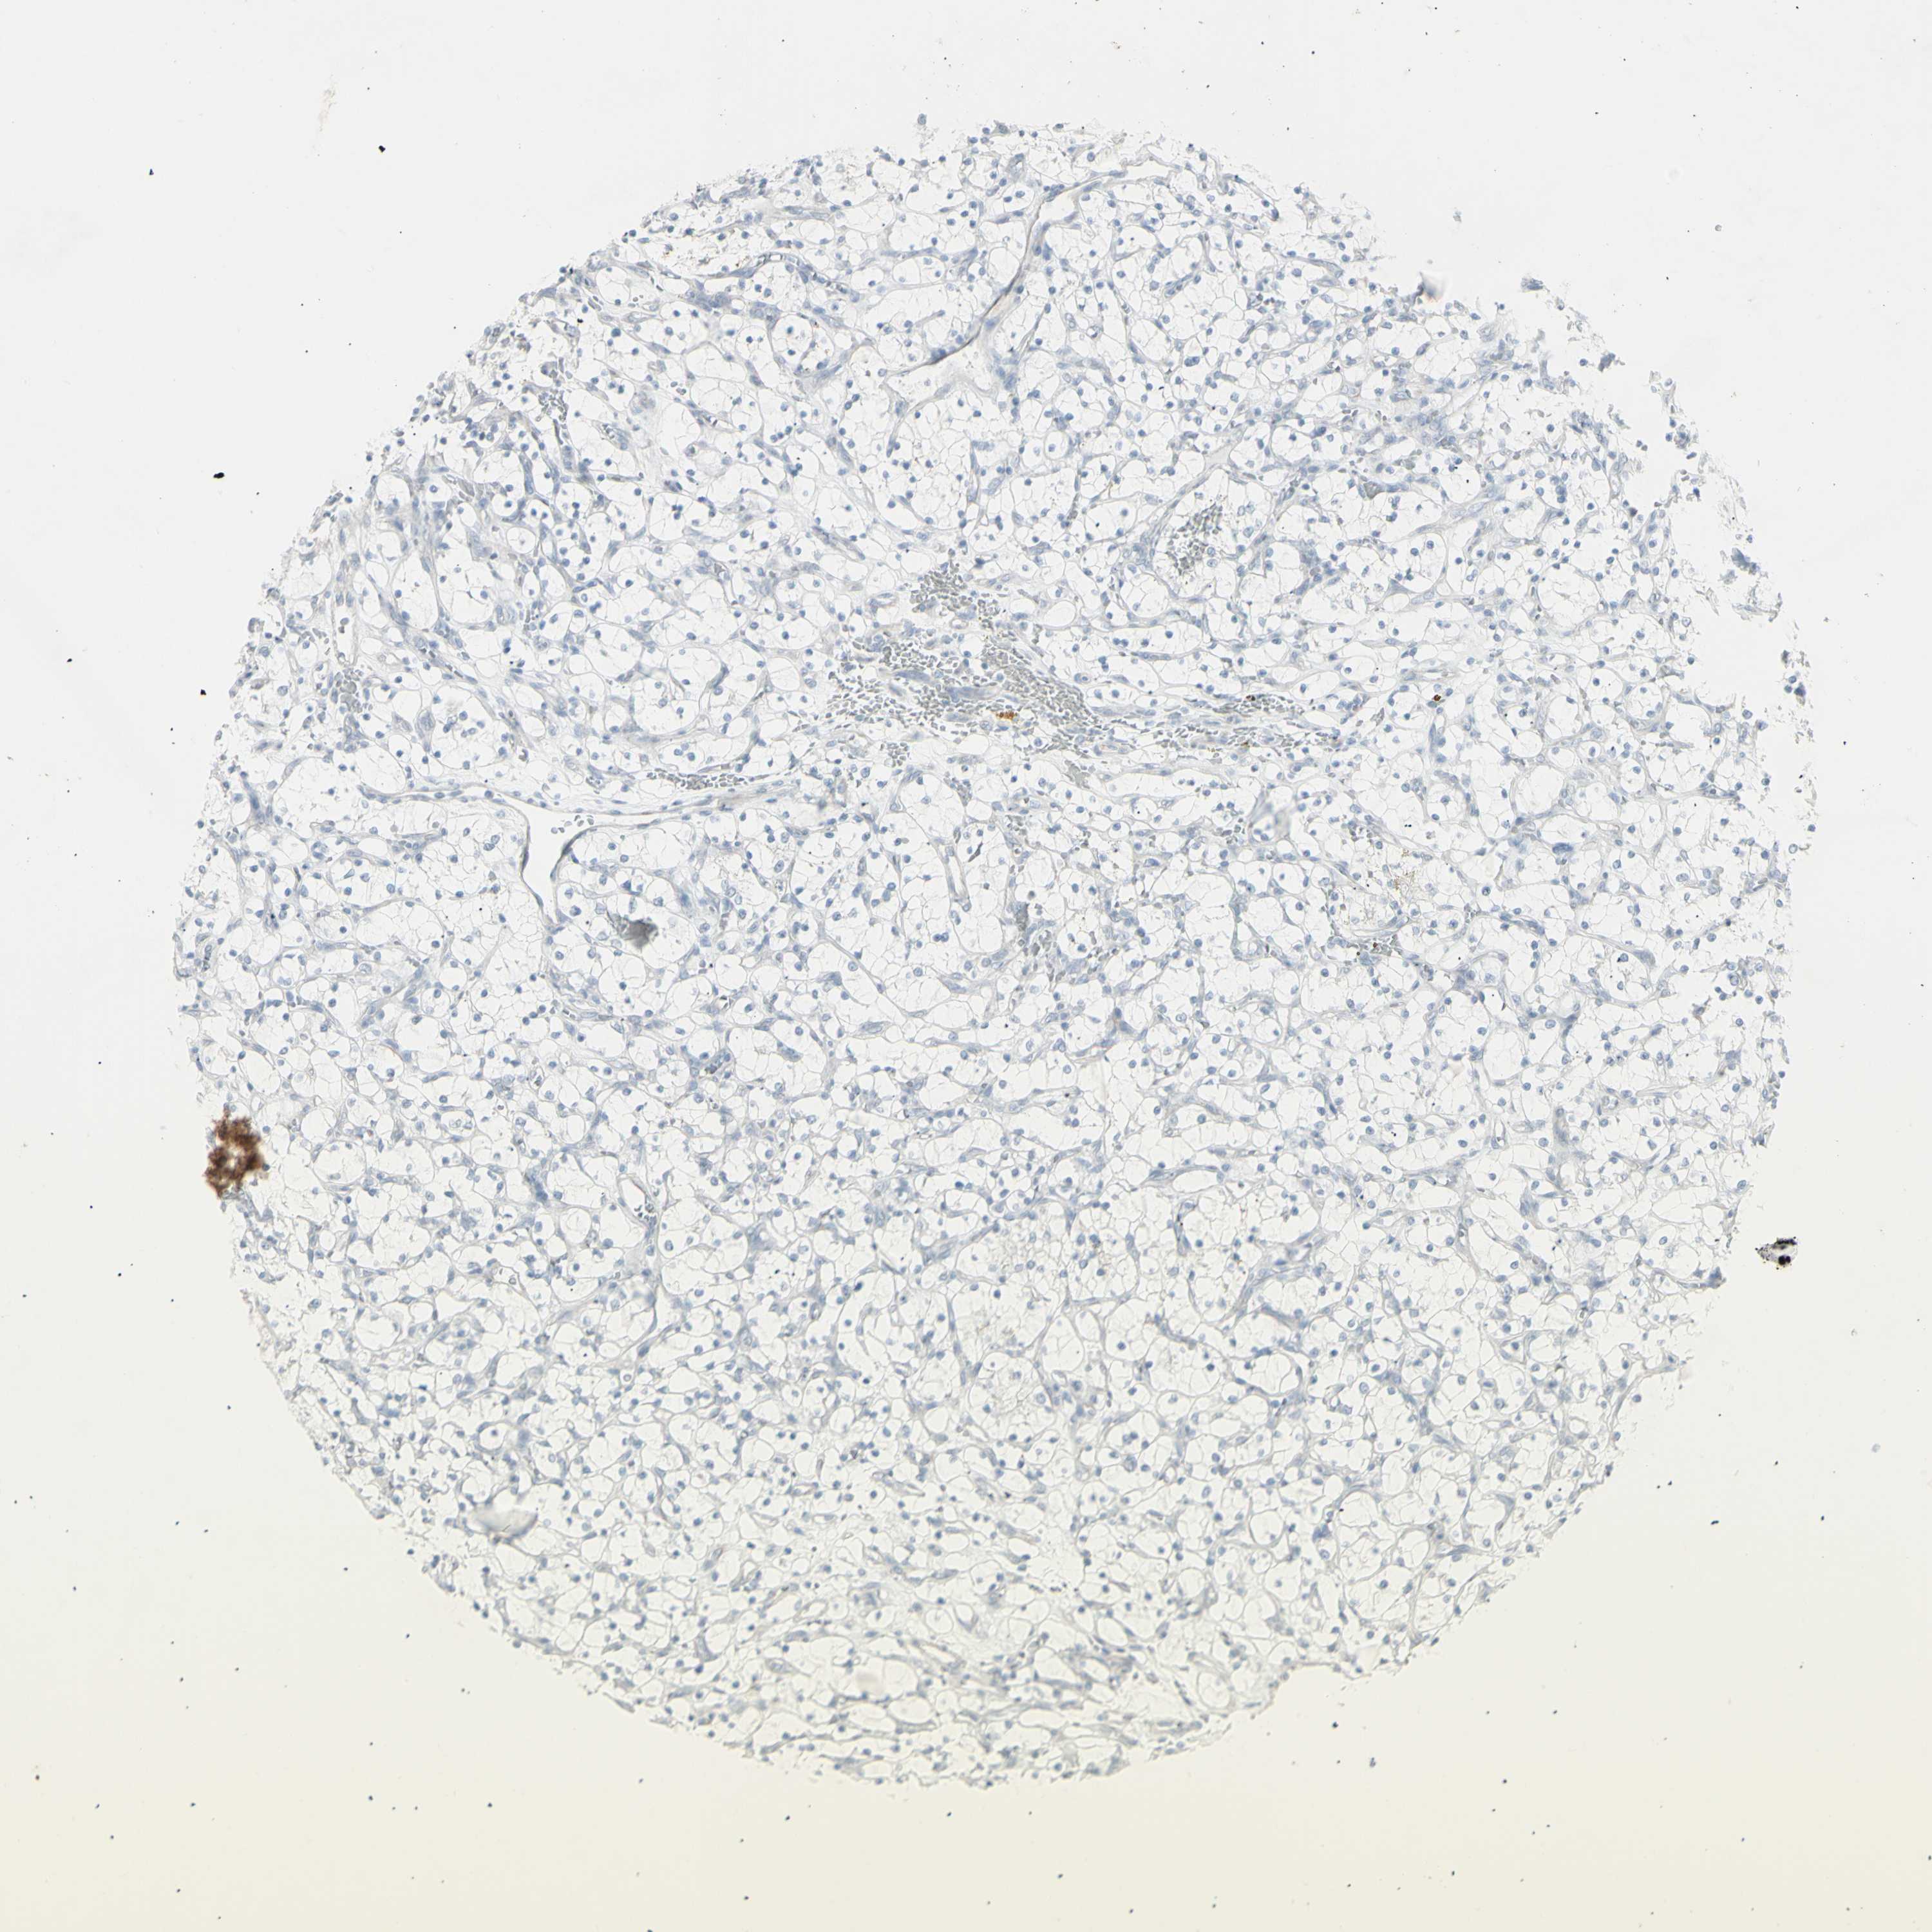

KIDNEY RENAL CLEAR CELL CARCINOMA (VALIDATION) - Interactive survival scatter ploti

The Survival Scatter plot shows the clinical status (i.e. dead or alive) for all individuals in the patient cohort, based on the same data that underlies the corresponding Kaplan-Meier plots. Patients that are alive at last time for follow-up are shown in blue and patients who have died during the study are shown in red.

The x-axis shows the expression levels (FPKM) of the investigated gene in the tumor tissue at the time of diagnosis. The y-axis shows the follow-up time after diagnosis (years). Both axes are complimented with kernel density curves demonstrating the data density over the axes. The top density plot shows the expression levels (FPKM) distribution among dead (red) and alive patients (blue). The right density plot shows the data density of the survived years of dead patients with high and low expression levels respectively, stratified using the cutoff indicated by the vertical dashed line through the Survival Scatter plot. This cutoff is automatically defined based on the FPKM cutoff that minimizes the p-score. The cutoff can be changed by dragging the vertical line or by entering a cutoff value in the square labeled "Current cut-off".

Under the Survival Scatter plot the p-score landscape (black curve; left axis) is shown together with dead median separation (red curve; right axis). Dead median separation is the difference in median mRNA expression between patients who have died with high and low expression, respectively. It is calculated as follows: median FPKM expression of dead patients with high expression - median FPKM expression of dead patients with low expression. This is intended to aid the user in visually exploring custom cutoffs and the associated p-scores and dead median separation.

Individual patient data is displayed and can be filtered by clicking on one or more of the category buttons on the top of the page. Categories describing expression level and patient information include: high, low, alive, dead, female, male and tumor stages. The scale of the x-axis can be toggled between linear and log-scale by clicking on the "x log" button. Mouse-over function shows TCGA ID, patient information and mRNA expression (FPKM) for each patient.

& Survival analysisi

Kaplan-Meier plots summarize results from analysis of correlation between mRNA expression level and patient survival. Patients were divided based on level of expression into one of the two groups "low" (under cut off) or "high" (over cut off). X-axis shows time for survival (years) and y-axis shows the probability of survival, where 1.0 corresponds to 100 percent.

YBX2 is not prognostic in Kidney Renal Clear Cell Carcinoma (validation)

TCGA RNA samplesi

RNA-seq data is reported as average FPKM (number Fragments Per Kilobase of exon per Million reads), generated by the The Cancer Genome Atlas (TCGA) .

Normal distribution across the dataset is visualized with box plots, shown as median and 25th and 75th percentiles. Points are displayed as outliers if they are above or below 1.5 times the interquartile range. FPKM values of the individual samples are presented next to the box plot.

Average pTPM 0.5

Number of samples 100